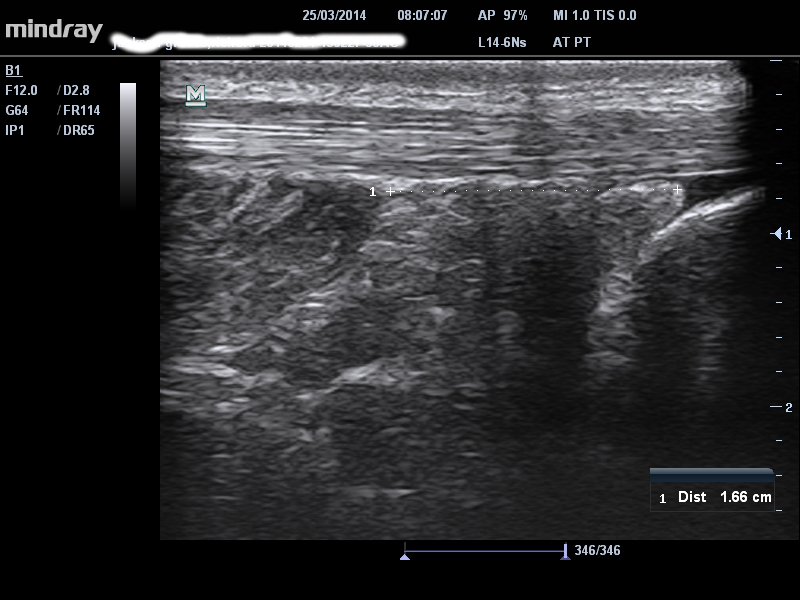

SÓLEO ACCESORIO

El músculo soleo accesorio es muy raro. He visto 4-5 en diez años. Por lo general, se presenta con dolor alrededor del tendón de Aquiles, pero en una inspección más cercana es más profundo al tendón de Aquiles. Hay un bulto muscular obvio de profundidad muy baja en el tendón de Aquiles tanto en el lado medial como en el lateral y con frecuencia es sensible a la palpación. El principal signo de diagnóstico diferencial es que el dolor empeora con la actividad y no se calienta con la actividad, similar al síndrome compartimental. El ultrasonido es muy útil para confirmar que hay un sóleo bajo (o accesorio). Nuestro paciente en la imagen de abajo tenía un sóleo distal a una longitud superior de 1.6 cm del calcáneo, mientras que la mayoría de las personas tiene al menos 3-4 cm. Este hombre había sido diagnosticado erróneamente y ¡le aplicaron 2 inyecciones de PRP a un tendón normal! Se dice que un verdadero sóleo accesorio se inserta en el calcáneo– nunca lo he visto. Entonces, tal vez la variante más común que he descrito aquí debería llamarse ‘sóleo bajo’.

single-image

8 – distancia de 1.66 cm entre el sóleo distal y el calcáneo proximal en un paciente con sóleo accesorio sintomático